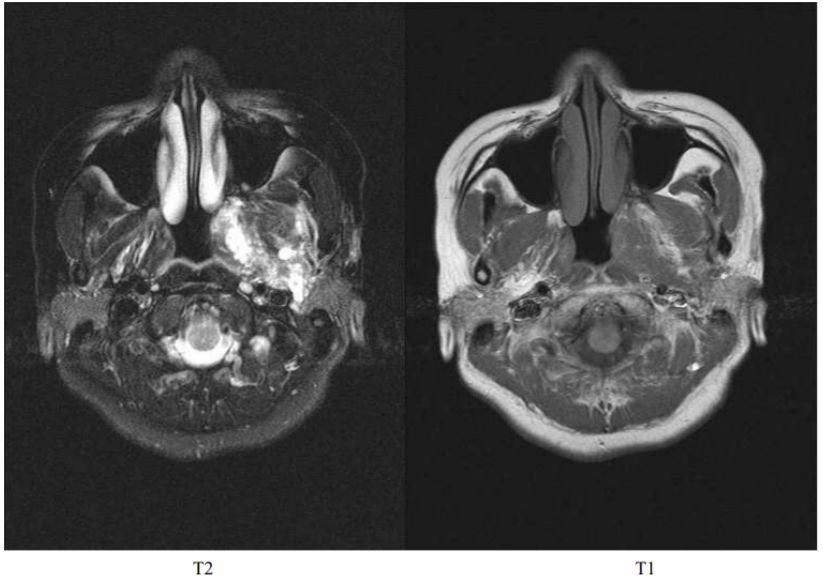

65.15歲少女左側臉部和口腔有許多長得很慢的腫塊,全身皮膚有café-au-lait的spots, 在pterygoid space的腫瘤 MRI的影像中,呈現T1沒有signal而T2有high signal(如附圖),則此腫瘤最可能是:(A)神經纖維瘤病(neurofibromatosis) (B)多形性腺瘤(pleomorphic adenoma) (C)造釉細胞瘤(ameloblastoma) (D)瓦新氏腫瘤(Warthin's tumor)